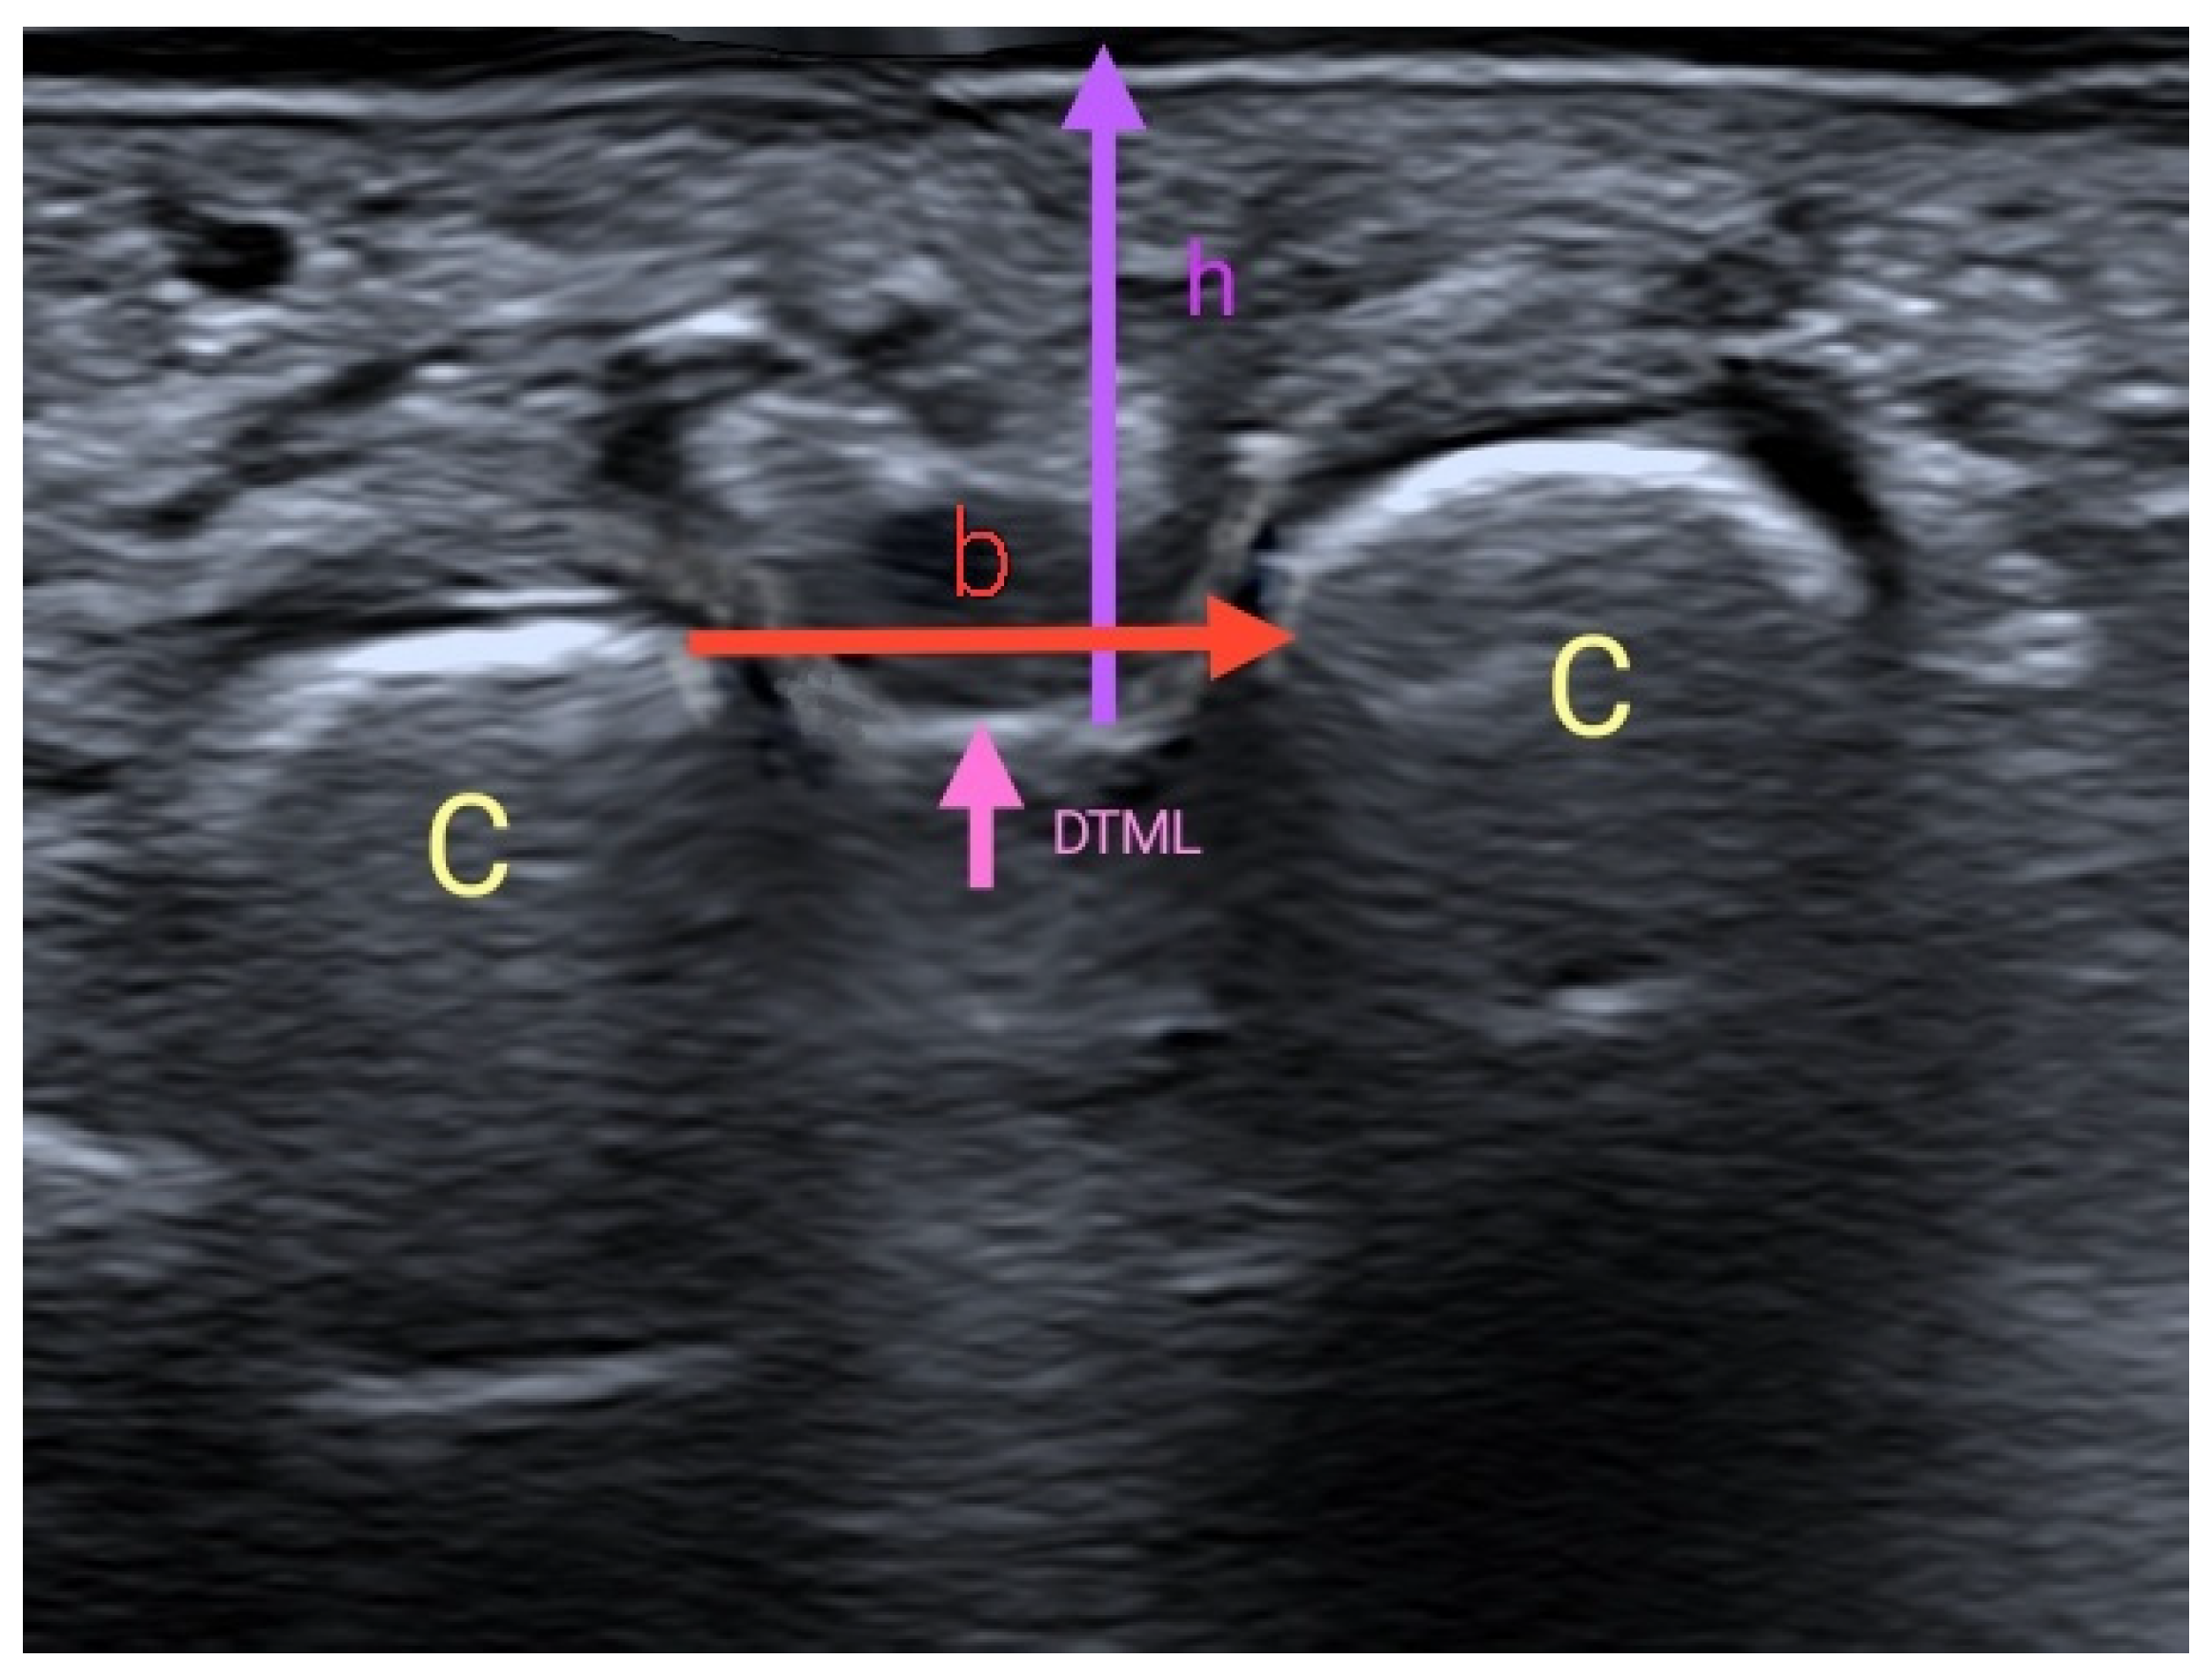

Novel Ultrasound Anatomical Measurement of the Deep Transverse Metatarsal Ligament: An Intra-Rater Reliability and Inter-Rater Concordance Study